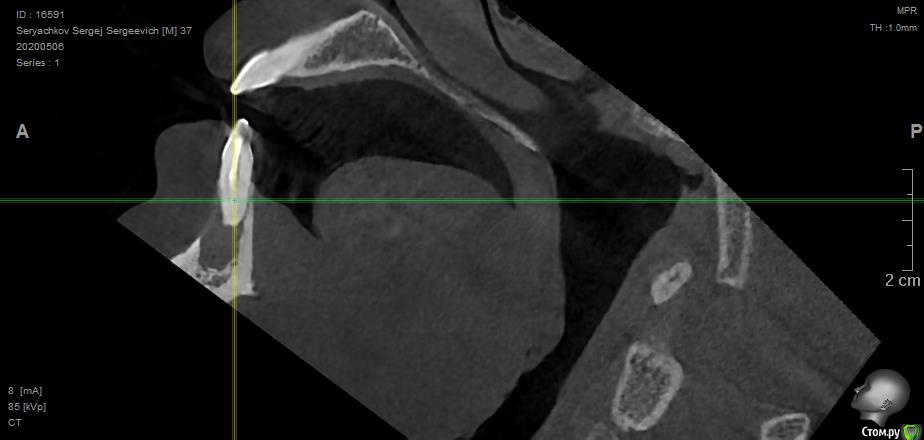

Под передними резцами обнаружилась обширная киста. В трёх клиниках предложили различное решение, но все основаны на удалении двух зубов, под которыми киста. Есть ли вариант сохранить и полечить зубы или удаление неизбежно?